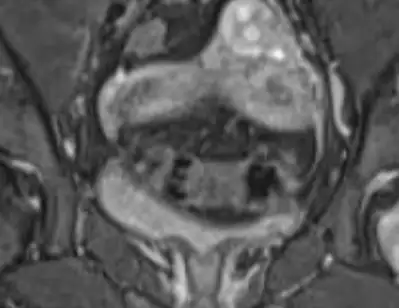

soldaki benim sagdaki senin. Ikisi de rahim perdesi olarak geçiyor ve bu rahim bebegin buyumesi için uygun sekilde degil demek oluyorYa senin yazinda gordm de perde ameliyati oldm demissin. Bende de bicornuat uterus var. Ilk ogrendigimde doktr perde var sende gibi bise de demisti sanki die hatirliorm. Gerci ondn sonra da hic doktora gitmedm. Dusuk ihtimali yuksk onun disinda bi sorun olmaz demişlerdi. Bi gitsm mi acaba napsam bilemedm

Bende universitedryken tesadufen ogrendm o zmn doktr dusuk ihtimali yuksk su an bise yapilmaz 3 tane dusuk yaptiktn sonra anca ameliyat yapiolarms. Bide korunma ztn zor olck gebeliklern demisti. Intrnettn fln bakiorm da gebelige engel deil sadece dusuk oluyo yazio. Hemen gidince ilk muayneden sonra yapiolar misoldaki benim sagdaki senin. Ikisi de rahim perdesi olarak geçiyor ve bu rahim bebegin buyumesi için uygun sekilde degil demek oluyor

Bicornute gibi degil de senin de uterus septuma benziyor aslinda ama ben anlamam tabi işin uzmani değilim doktor daha iyi bilir

Mr sonucunda yazio bikornual uterus die.Bicornute gibi degil de senin de uterus septuma benziyor aslinda ama ben anlamam tabi işin uzmani değilim doktor daha iyi bilir